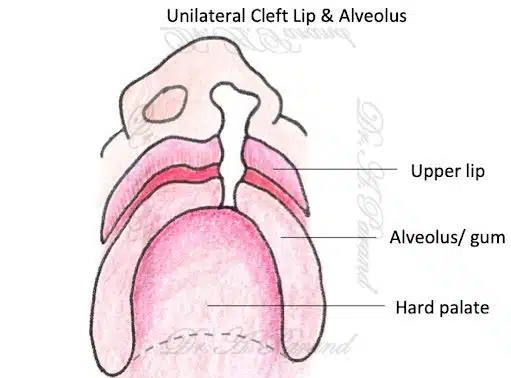

شکاف آلوئولار چیست؟

شکاف آلوئولار یک نقص مادرزادی است که در آن بخشی از دهان و فک بالا بهطور کامل تشکیل نمیشود. این شکاف معمولا بین دندانها و لثهها قرار دارد و ممکن است به بینی نیز متصل باشد. این مشکل میتواند به مشکلات تغذیه، گفتار و حتی تنفس منجر شود.

تشخیص شکاف آلوئولار معمولا در زمان تولد و از طریق معاینه فیزیکی انجام میشود. در برخی موارد، این مشکل ممکن است در دوران بارداری و از طریق سونوگرافی شناسایی شود.

جراحی شکاف آلوئولار چگونه انجام میشود؟